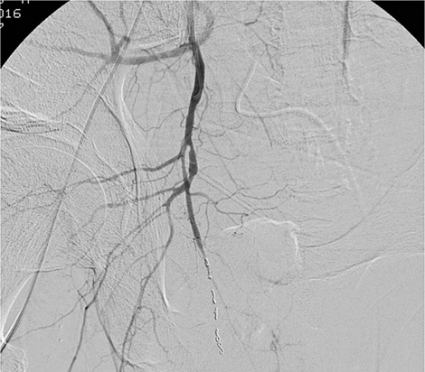

• Angiografiundersökning av bäckenkärlen genomförs om sådan facilitet är tillgänglig (Figur 3) [11]. Det bör observeras att angiografi är ett tidskrävande ingrepp, som bör utföras innan patienten blir hemodynamiskt »för dålig«.

4. Patienter som varit in extremis och behandlats med bäckenpackning men fortsätter att blöda kontrollerat (jämför grupp 2). Angiografiundersökning genomförs; hos 80 procent av dessa patienter finner man positivt fynd [9] tydande på större arteriell skada. Detta innebär att packning kontrollerar i huvudsak större venösa blödningar, medan arteriella blödningar kan minskas men ofta inte helt tamponeras.